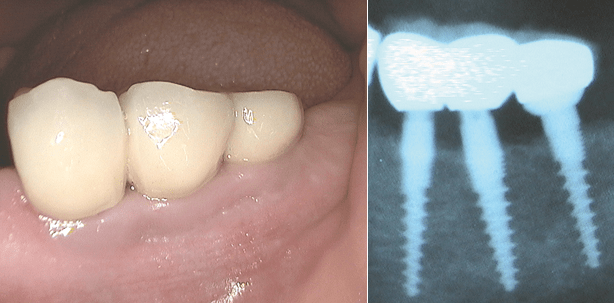

Im November 2009 implantierten wir in der Region 15,16. Die klinischen Aufnahmen der Nachkontrolle erfolgten im Januar 2015 (Abb. 12 bis 15).

Beurteilung

Diese triangulierten Insertionen vermeiden wir heute, da sich die „Schmutznischen“ als nicht handelbar erwiesen haben. Eine strenge mesial-distal orientierte Implantat-Ausrichtung auf Kieferkammmitte ist anzustreben. Trotzdem ist die klinische Situation nach über 5 Jahren hervorragend.